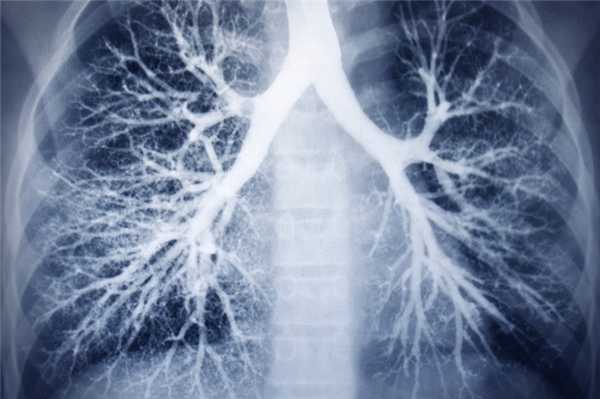

Стандартное рентгенологическое исследование, дополненное иногда бронхографией, позволяет поставить правильный диагноз. В отличие от хронического бронхита, бронхоэктазы в значительной части случаев видны на обзорных рентгенограммах и томограммах. Наиболее часто бронхоэктазы встречаются в нижней доле слева и в средней доле справа.

При поражении нижней доли слева возникает характерная рентгенологическая картина (М. Г. Виннер и соавт., 1969): смещение левого корня книзу; разрежение легочного рисунка из-за вздувшейся верхней доли (компенсаторное вздутие); смещение сердца влево, сужение нижнего легочного поля; смещение книзу и кзади главной междолевой щели, что лучше видно на боковых рентгенограммах и томограммах; затемнение и уменьшение размеров самой нижней доли. При этом срединная тень сердца приобретает двойные контуры: латерально проецируется контур тени сердца, а медиально - контур уменьшенной нижней доли. Величина треугольной тени нижней доли зависит от степени ее спадения. Пятнисто-тяжистое затемнение у верхушки левого желудочка свидетельствует о наличии воспалительного процесса в нижней доле слева и язычке. При резко уменьшенной нижней доле, которая в таких случаях прячется за тенью сердца, эти патологические тени образуются воспалительным процессом в язычке. При изолированном поражении нижней доли или нижней зоны и их резком спадении, когда изображение пораженного отдела полностью располагается за тенью сердца, этих патологических изменений не видно. Также характерно затемнение в области заднего реберно-диафрагмального синуса, что видно на боковых томограммах и рентгенограммах. Этот признак является одним из самых постоянных и часто встречающихся.

При Бронхографии обнаруживается, что бронхи нижней зоны или доли расширены и сближены между собой. Бронхи язычка и остальных сегментов верхней доли смещены и раздвинуты. При вовлечении в воспалительный процесс язычковых бронхов они также цилиндрически расширены и сближены между собой и с бронхами нижней доли. Бронхи верхней зоны веерообразно раздвинуты.

При поражении средней доли на обзорных рентгенограммах отчетливо определяются лишь кистовидные бронхоэктазы; другие формы отображаются в виде более или менее выраженного усиления и деформации легочного рисунка.

На томограммах в боковой или косой проекции пораженная доля бывает неоднородно затемнена, в ней наблюдаются множественные, округлые или линейные просветления, являющиеся отображением просвета расширенных бронхов в продольном, поперечном и косом сечениях.

На томограммах мешотчатые и кистовидные бронхоэктазы верхней доли отображаются в виде множественных округлых и овальных полостей с более или менее тонкими стенками, которые располагаются своей длинной осью по ходу соответствующих бронхов. В части случаев их контуры нечеткие, что обусловлено склеротическими изменениями. Иногда кистовидные бронхоэктазы сочетаются с воздушными бронхиальными кистами. Томографическая картина у них неотличима. Ценным методом, делающим возможным их распознавание, является бронхография. В отличие от воздушных бронхиальных кист, кистовидные и мешотчатые бронхоэктазы хорошо контрастируются.